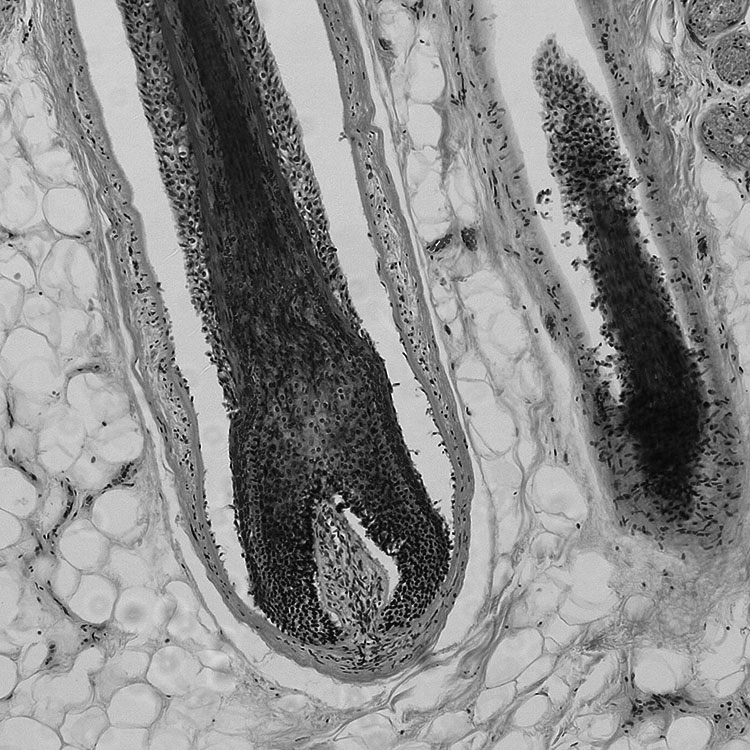

Les mécanismes biologiques du refroidissement du cuir chevelu. La recherche biologique sur le refroidissement du cuir chevelu s'est concentrée sur l'exploration de l'hypothèse selon laquelle le refroidissement réduit l'entrée des médicaments de chimiothérapie dans les kératinocytes humains.